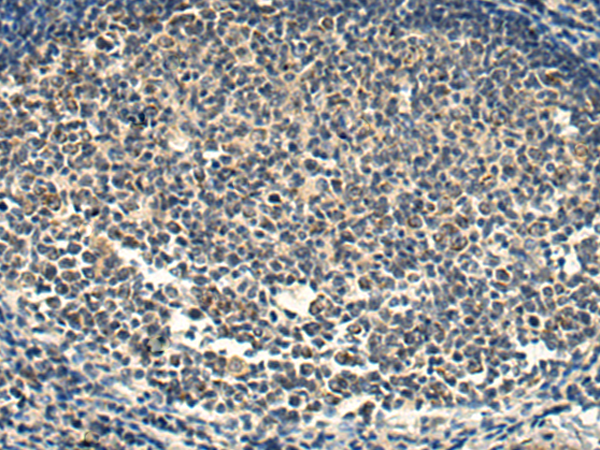

图片:

The image is immunohistochemistry of paraffin-embedded Human colorectal cancer tissue using (SNAP47 Antibody) at dilution 1/220.

,

The image is immunohistochemistry of paraffin-embedded Human tonsil tissue using (SNAP47 Antibody) at dilution 1/220.